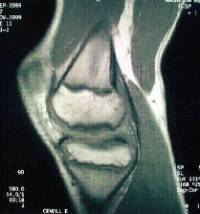

Es una patología ocasionada por una isquemia transitoria del hueso subcondral pudiendo progresar hasta llegar a provocar el desprendimiento del mismo.

Se localiza con mayor frecuencia en el cóndilo femoral interno y su pronóstico varía en función de la edad de presentación (poco frecuente por debajo de los 10 años) y la estabilidad de la lesión.

El tratamiento pasa por limitar actividad deportiva de impacto , variar el eje de carga mecánico de la extremidad y puede ser necesaria la intervención quirúrgica.

Existen diferentes opciones de tratamiento quirúrgico en función de la estabilidad y localización del fragmento osteocondral (microperforaciones bajo control artroscópico , fijación in situ del fragmento osteocondral , empleo de injertos osteocondrales / mosaicoplastia ).